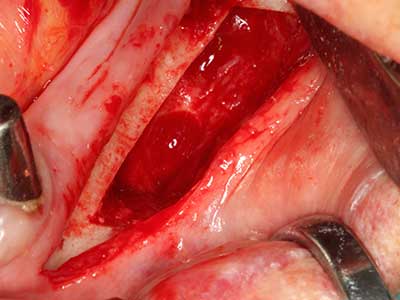

En la extracción de bloques óseos la piezocirugía también presenta ventajas adicionales: Además de la alta precisión en la osteotomía que ya se ha descrito antes, se ha comprobado que el uso de los delgados insertos de sierra resulta especialmente cuidadosas con el hueso. Frente a esto, sobre todo cuando se usan las fresas de Lindemann, cabe esperar pérdidas en la extracción significativamente más altas debido al mayor grosor de la parte frontal del cabezal (Lakshmiganthan, Gokulanathan et al. 2012). La separación basal que se necesita en particular en los injertos de bloque extraídos de forma retromolar se ve facilitada mediante sierras perpendiculares especialmente previstas a tal fin, lo que permite considerar que la cirugía piezoeléctrica es un procedimiento preciso y seguro para la obtención de bloques de hueso en el área retromolar (Happe 2007) (fig. 1-12).